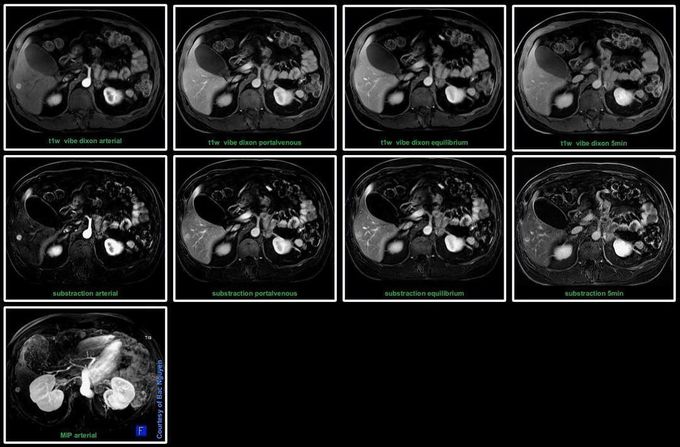

MRI Liver Imaging – Dynamic phase @ Siemens 3T Prisma Dynamic phase is a vital part of the liver imaging protocol due to its greater diagnostic accuracy. Given the distinctive liver physiology and its dual blood supply, dynamic enhancement patterns for a particular disease on the different phases of liver enhancement can narrow the differential diagnosis. Case; Metastasis utilizing extracellular contrast agent.#Siemens_MRI #siemens #mri #gadolinium #liver_imaging